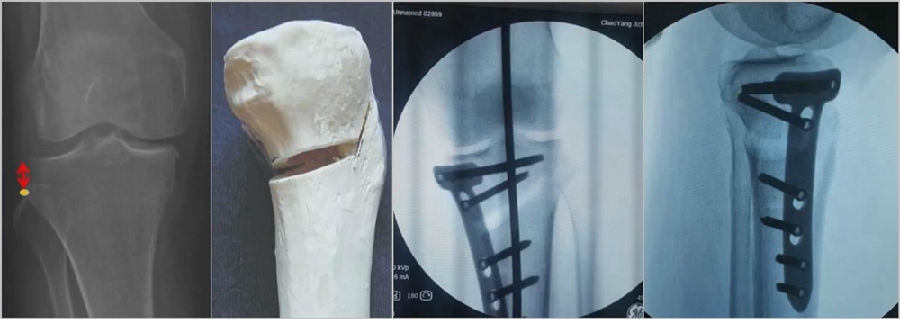

一、合页骨折

合页骨折分为3型:Ⅰ型,骨折是截骨线的延伸,位于上胫腓关节近段或刚好位于上胫腓关节;Ⅱ型,骨折延伸到上胫腓关节的远端;Ⅲ型截骨线通向外侧胫骨平台,也可以称为胫骨外侧平台骨折。

合页骨折分型

2、处理

(1)Ⅰ型骨折

因为外侧合页周围有软组织,即使是说骨性合页断了,但是由于软组织合页还在,所以只要用拉力螺钉复位固定,维持好力线即可。术后患者正常康复,预后较好。

(3)Ⅲ型骨折

首先要把截骨撑开钳拿下来,此时骨折端会自动复位,然后再由外向内侧打入一颗拉力螺钉,将胫骨平台做临时固定,然后再进一步的用摆锯锯或是用骨刀打,保留1cm的合页,最后再进行撑开,做内固定。同样要求患者做结构植骨加延迟负重。

截骨偏前,截骨线过短;Ⅲ型骨折;保留1cm合页

结构植骨,外侧拉力钉固定

3、总结:合页骨折的原因及处理

Ⅰ型:合页点过高、截骨线过深,无需特殊处理,拉力钉加压,正常康复。

Ⅱ型:合页点位置过低、拉力钉过度加压,拉力钉复位,钢板固定,结构植骨,延迟负重。

Ⅲ型:合页保留过宽,外侧平台复位,拉力钉固定,继续截骨,钢板固定,结构植骨,延迟负重。